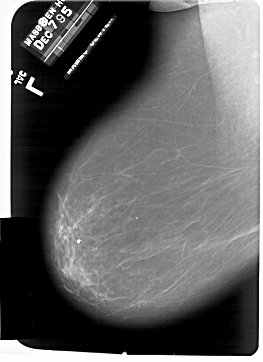

A_1863_1.LEFT_CC

LEFT_CC LINES 6646 PIXELS_PER_LINE 5086 BITS_PER_PIXEL 12 RESOLUTION 43.5 NON_OVERLAY